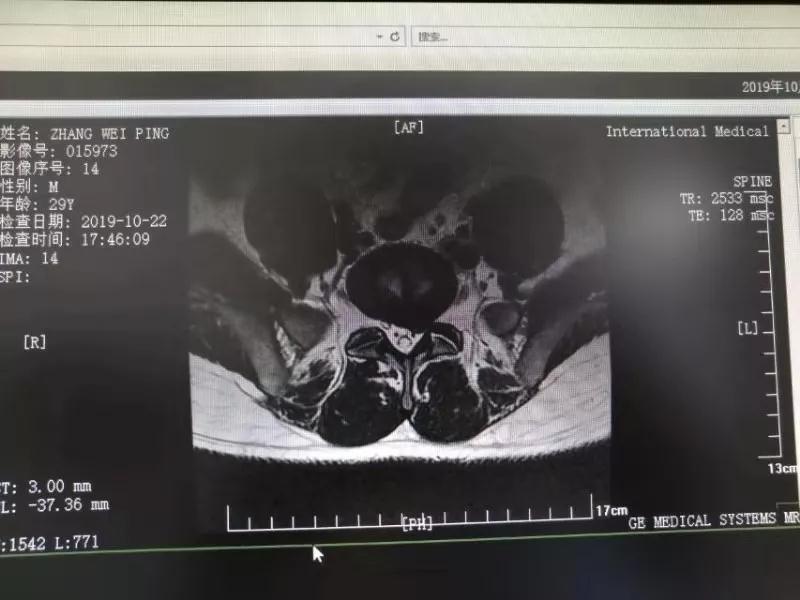

10月25日,29歲的患者小張了解到西安國際醫(yī)學(xué)中心骨科醫(yī)院專家云集,一大早便在家人的陪同下,來到西安國際醫(yī)學(xué)中心骨科醫(yī)院就診?!拔已闯掷m(xù)2年多,最近感冒后腰痛癥狀明顯加重了?!毙埫媛犊喑驗殚L期腰痛、左下肢放射性疼痛,她晚上睡覺不能平躺,經(jīng)常疼得睡不著,需要口服止痛藥物才能有所緩解。走路走不了多遠(yuǎn)就開始腿抽的疼,嚴(yán)重影響到工作和生活。

結(jié)合患者的檢查以及年齡情況,王自立副院長推薦讓專門研究椎間孔鏡技術(shù)王雄勛主任給小張做微創(chuàng)的椎間孔鏡手術(shù)。該手術(shù)創(chuàng)傷很小,不影響脊柱的穩(wěn)定性,尤其適合于椎間盤突出的年輕患者,懷著對骨科醫(yī)院專家的信任,小張與家人商議后,接受手術(shù)治療。